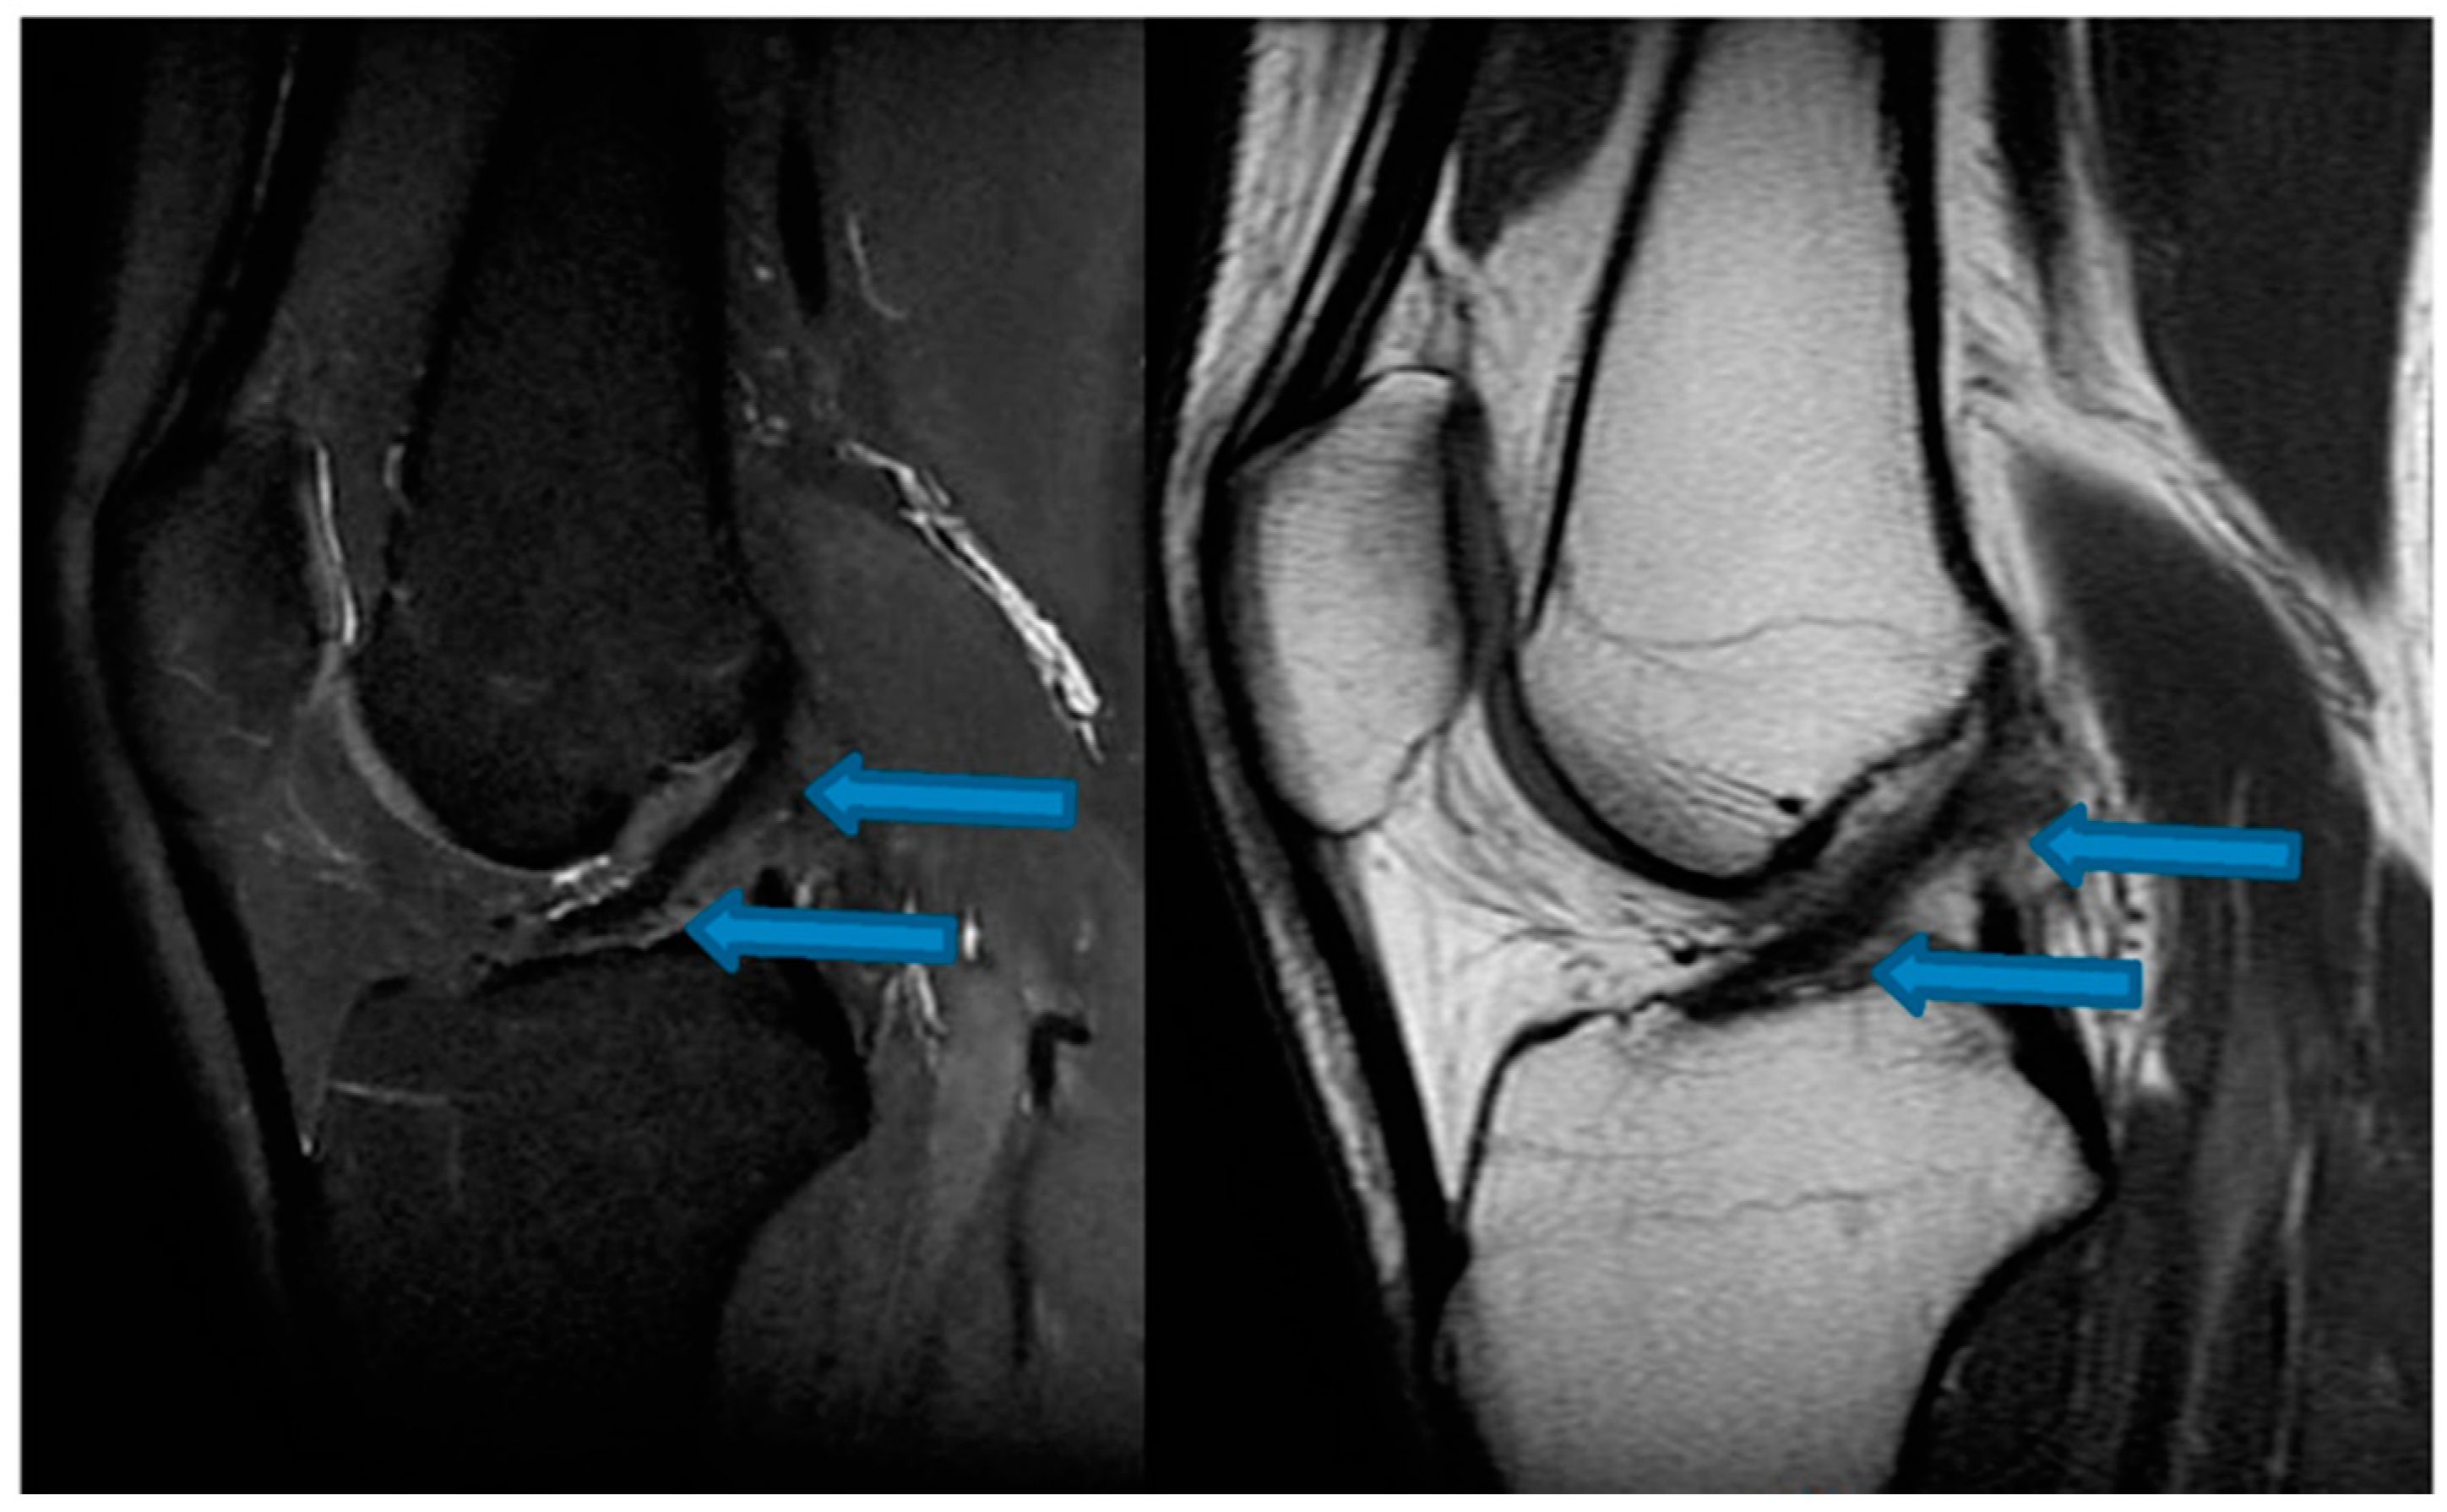

| 9 November 2020 | MRI scans demonstrating signs of partial ACL healing |

| 14 August 2021 | MRI scans demonstrating signs of complete ACL healing |

| 24 December 2021 | MRI scans confirming signs of complete ACL, MCL and medial meniscus healing |